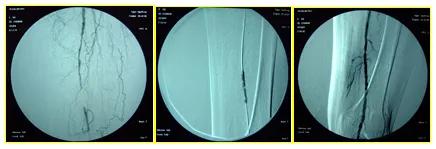

部分严重的患者,需要采取腔内治疗和手术治疗。腔内治疗也被称为微创介入手术, 是指用特殊的穿刺针穿刺动脉,从这个穿刺处放入一些特殊的导丝和导管,在X线的监视下,到达病变血管,用球囊扩张狭窄动脉,然后用特制的金属支架支撑狭窄部位,达到扩大下肢动脉管腔、恢复肢体血流的治疗目的。腔内治疗是一种微创手术,治疗后只在腹股沟处留下一个极小的针眼,对血管以外的任何组织不造成伤害,创伤小,痛苦少,恢复快,24小时可下床活动。